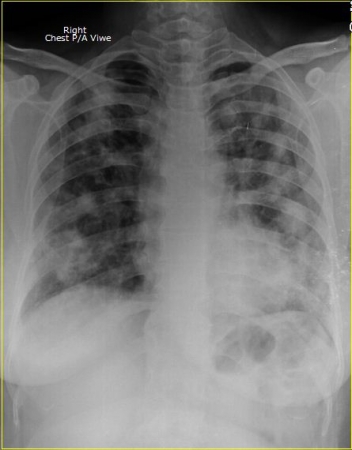

ইহা একটি বুকের এক্সরে। যাকে ডাক্তারী বাসায় বলা হয় Chest Posterior/Anterior Viwe.

রোগীর নামঃ সুগেরা বেগম। বয়সঃ ৫০ বছর।

রোগীটি নিজেও জানে না সে করোনা আক্রান্ত, সার্জারী ডাক্তার দেখাতে এসেছিল এবং গল ব্লাডার এর অপারেশন জন্য প্রস্তুতি নিচ্ছিলো। ডাক্তার তার স্বাস্থ্যের সকল অবস্থা দেখার জন্য কিছু রক্ত পরিক্ষার সাথে এই এক্সরে টি দিয়েছিল। পরীক্ষাটি করার পর আমি রীতিমতো অবাক হয়ে গেলাম। রিপোর্ট টি ডাঃ অরুন কুমার পাল কে দেখালাম। তিনি অতিদ্রুত সদর হাসপাতাল এ করোনা ইউনিটে পাঠিয়ে দিলেন।

আসুন সচেতন হই। এবং নিয়মিত স্বাস্থ্য পরিক্ষা করে দেহের ভেতরের সকল অংশের খোজ খবর রাখি। যে পরীক্ষাটি করালে আপনারা মোটামোটি ধারণা পাবেন, বা আপনার ফুসফুসে করোনা ভাইরাসের উপস্থিতি আছে কি নেই। সেটি হলোঃ CXR P/A Viwe. কারণ ভাইরাসটির প্রধান খাবার হচ্ছে ফুসফুস বা LUNGS ।আর এই পরিক্ষাটি জুড়েই রয়েছে ফুসফুসের অবস্থান।

আপনাদের বোঝার সুবিধার্থে আক্রান্ত রোগীর বুক ও সাধারণ রোগীর বুকের দুইটি এক্সরের ছবি নিচে দেওয়া হলোঃ

করোনা আক্রান্ত রোগীর ফুসফুস বা LUNGS।